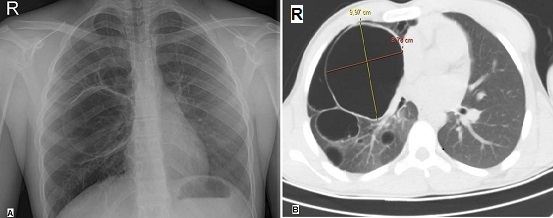

A 15-year-old previously healthy boy was involved in a traffic accident and presented to our emergency department (ED) with complaints of chest pain and mild shortness of breath. On physical examination, he had complained for the last 2 hours of the right hemithorax pain in the fifth intercostal space radiating to the right midaxillary line. He had no past medical or surgical history. Chest x-ray demonstrated doubtful multiple thin-walled cystic lesions in the right lung (A). Computed tomography (CT) scan of thorax revealed a well- defined thin-walled, and 9.97 x 8.78 cm in diameter giant air cyst occupying the right upper lobe parenchyma with multiple air-space cysts (B). The patient was finally diagnosed as a multiple cystic lung disease and he underwent elective thoracic surgery for cyst removal. Cystic lung disease is defined as intrapulmonary air-containing multiple cysts surrounded by sharply demarcated thin walls. CT scanning of thorax is more sensitive than chest radiography in the detection and the distribution of lung cysts. Patients with cystic lung disease may be asymptomatic or present with nonspecific symptoms, such as chronic cough or shortness of breath. They are at increased risk for spontaneous pneumothorax. Surgical treatment of multiple cystic lung disease plays a crucial role in the prevention of pneumothorax.